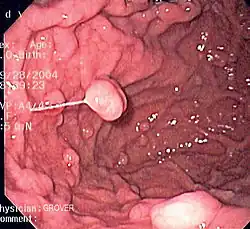

Diseases

A series of radiographs can be used to examine the stomach for various disorders. This will often include the use of a barium swallow. Another method of examination of the stomach, is the use of an endoscope. A gastric emptying study is considered the gold standard to assess the gastric emptying rate.[50]

A large number of studies have indicated that most cases of peptic ulcers, and gastritis, in humans are caused by Helicobacter pylori infection, and an association has been seen with the development of stomach cancer.[51]